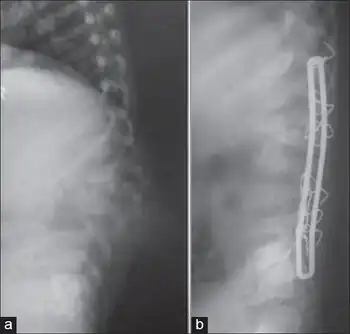

Kyphosis progression prevention

Lateral X-ray of lumbosacral spine a) shows TB of L1–L3 with kyphosis of 40°; b) lateral X-ray of same individual where lumbar kyphosis is corrected with pedicle subtraction and Hartshill fixation

Surgical intervention is used in patients with kyphosis to primarily prevent the progression of kyphosis in active disease and correct it to a certain extent.[29]

However, surgical intervention is not meant to cure kyphosis in the patient and has variable rates of success in eradicating it in a patient.[29]

In the event that a patient shows signs of kyphosis, the earlier surgical intervention is given, the better the outcome for the patient.[29]